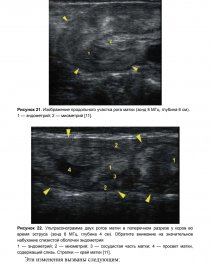

Гипофункция яичников связана с анэструсом и характеризуется отсутствием больших фолликулов без желтого тела и наличием небольших фолликулов диаметром менее 4 мм (рис. 1).

Рисунок 1. Ультразвуковое изображение гипофункции яичника (зонд 7,5 МГц, глубина 2,5 см). Обратите внимание на наличие большого количества мелких фолликулов (менее 4 мм) вокруг стромы яичника.

1 — фолликул; 2 — строма яичника [11].

Склероз яичников предопределяется более глубокими морфологическими изменениями тканей (рис. 3). На эхограмме видно, что яичник приобретает округлую форму. Оболочка имеет повышенную эхогенность, а кортикальный пласт становится эхонегативным [1].